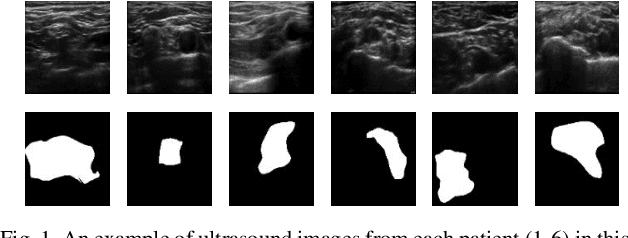

Abstract:Automated object recognition in medical images can facilitate medical diagnosis and treatment. In this paper, we automatically segmented supraclavicular nerves in ultrasound images to assist in injecting peripheral nerve blocks. Nerve blocks are generally used for pain treatment after surgery, where ultrasound guidance is used to inject local anesthetics next to target nerves. This treatment blocks the transmission of pain signals to the brain, which can help improve the rate of recovery from surgery and significantly decrease the requirement for postoperative opioids. However, Ultrasound Guided Regional Anesthesia (UGRA) requires anesthesiologists to visually recognize the actual nerve position in the ultrasound images. This is a complex task given the myriad visual presentations of nerves in ultrasound images, and their visual similarity to many neighboring tissues. In this study, we used an automated nerve detection system for the UGRA Nerve Block treatment. The system can recognize the position of the nerve in ultrasound images using Deep Learning techniques. We developed a model to capture features of nerves by training two deep neural networks with skip connections: two extended U-Net architectures with and without dilated convolutions. This solution could potentially lead to an improved blockade of targeted nerves in regional anesthesia.